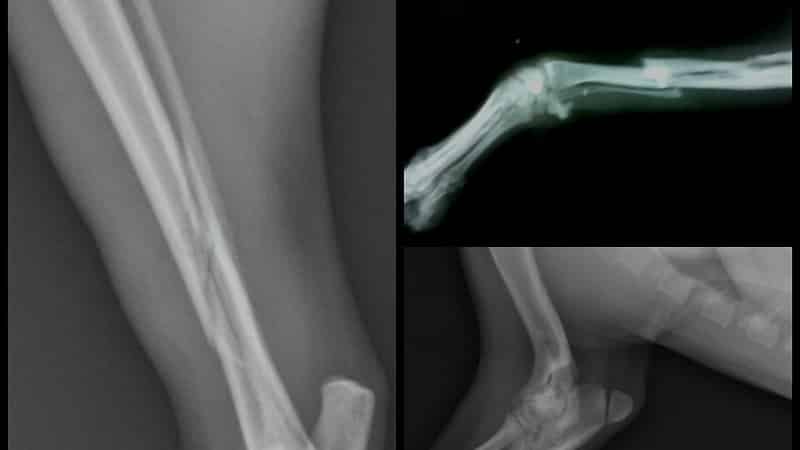

На приеме у хирурга или травматолога осуществляется первичный осмотр, фиксируются жалобы пациента, выясняется, каким образом была получена травма, и выдается направление на рентген. Этот метод диагностики трещин и переломов является стандартным и позволяет получить информацию о типе повреждения, увидеть, как выглядит трещина в кости на снимке, а также оценить ее размеры и состояние окружающих тканей.

Стратегия лечения зависит от точности диагноза. В сложных и тяжелых случаях для более детального определения характера повреждений применяется магнитно-резонансная томография, которая позволяет создавать трехмерные изображения с определением глубины повреждения кости.